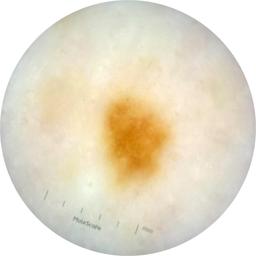

ISIC_9472333

Information

2057 x 2057

Clinical

Field Value

acquisition_day 230

age_approx 65

anatom_site_1 Trunk

anatom_site_2 Anterior trunk

anatom_site_general anterior torso

concomitant_biopsy False

diagnosis_1 Benign

diagnosis_confirm_type single image expert consensus

family_hx_mm True

fitzpatrick_skin_type I

image_manipulation instrument only

image_type dermoscopic

lesion_id IL_9967494

patient_id IP_4296977

personal_hx_mm True

sex female